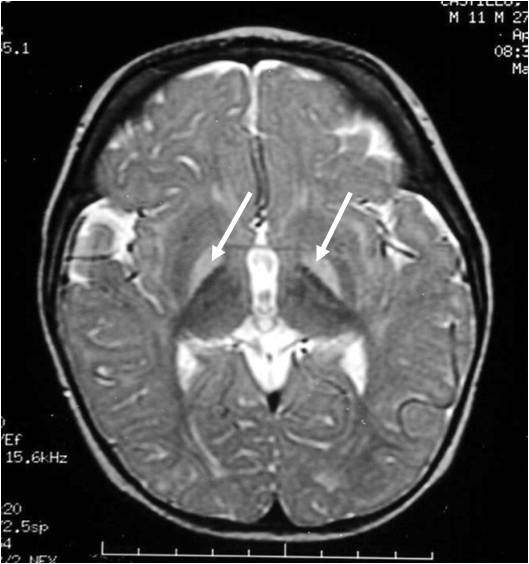

Brain Mri Kernicterus Brain Mri

From brainmrimorigen.blogspot.com

Brain Mri Kernicterus Brain Mri What Does The Medical Term Kernicterus Meaning Jaundice is a common condition that affects newborns, but if it becomes severe, it can cause permanent damage. Babies with this condition need to be treated right away to bring down their bilirubin levels and prevent further brain damage. It occurs when the unconjugated. The term kernicterus literally means yellow kern, with kern. Kernicterus is a medical emergency. Kernicterus is. What Does The Medical Term Kernicterus Meaning.

From radiopaedia.org

Kernicterus Image What Does The Medical Term Kernicterus Meaning Kernicterus is brain damage caused by severe, untreated jaundice or high blood levels of a substance called bilirubin. Kernicterus is a rare neurological disorder characterized by excessive levels of bilirubin in the blood (hyperbilirubinemia) during. It occurs when the unconjugated. Jaundice is a common condition that affects newborns, but if it becomes severe, it can cause permanent damage. Kernicterus is. What Does The Medical Term Kernicterus Meaning.